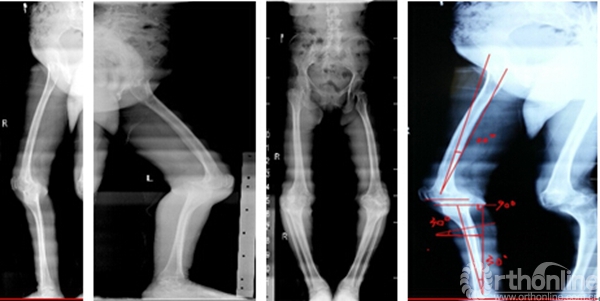

双下肢全长正侧位片

李某某,女,60岁,双侧膝关节疼痛、活动受限并伴股骨胫骨畸形40余年,其股骨远端前弓大,股骨前髁小,后髁大,胫骨近端后外弓30°,股骨髁及胫骨平台发育小,KSS评分15分,患者来我院就诊,要求行手术治疗改善外观及生活质量。

该患者躯干高度正常,四肢长度不成比例地短小,为短肢型侏儒,且股、胫骨变短和弯曲,干骺端异常,头面部正常,无典型三叉畸形,无腰椎椎弓根间距逐渐变小,智力及体力发育良好,家族中同代兄弟姐妹7人,其中3人类似病情,因此考虑该患者为家族型软骨发育不全型侏儒症合并双膝严重骨性关节炎(关节外畸形伴内翻)。

我们对患者进行64排螺旋CT扫描,轴向平面切片1mmx1mm,数据保存为DICOM格式,输入Materialise®三维建模软件,进行三维重建配准,三维建模软件重建后分析患者膝关节解剖结构、分析力线、外翻角、内外旋角和截骨面,模拟标准化手术程序,重建下肢力线,设计胫骨近端截骨矫形模块及股骨、胫骨平台、胫骨髓内干等模具,通过3D打印技术制作出1:1的患骨3D实物模型、手术导板及截骨模板。